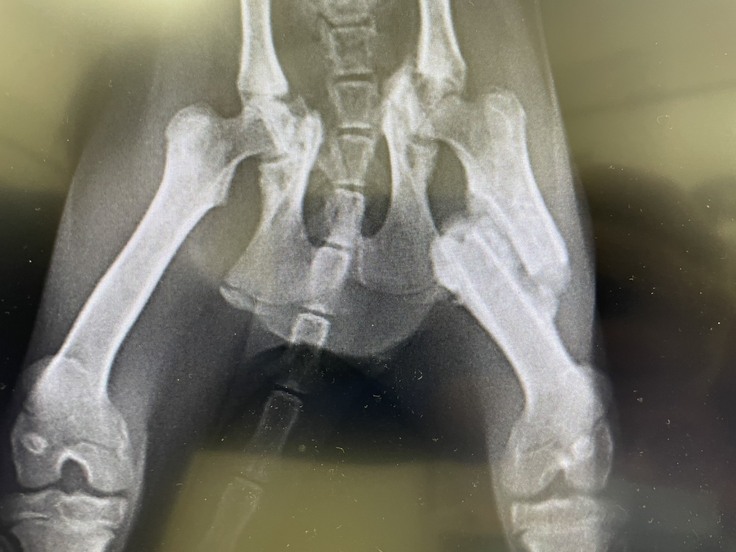

咲ちゃんは、骨盤と脚を骨折してから時間が経過していました。

折れたまま固まってしまっていたため、整復することができませんでした。

▼咲ちゃんのレントゲン画像

排泄も歩行もできますが、酷い折れ方をしているせいか、痛みを感じているようにも感じます。

断脚の可能性も視野に入れつつ、様子をみています。